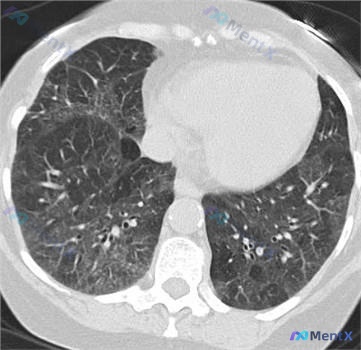

病例资料整理与讨论 整理了一份肺部肿瘤术后的病例资料,其中有几个影像与病理对照的点值得复盘。 患者信息:43 岁女性 主要经过:因右上叶支气管癌接受切除术 影像发现: 1. 右上叶可见类圆形实性结节/团块影(已证实为癌)。 2. 背景肺野存在广泛且复杂的病理改变:双肺弥漫性磨玻璃影(GGO),伴网格...